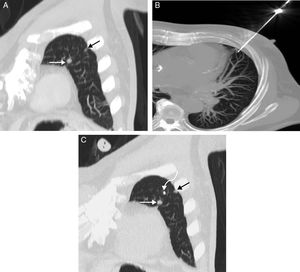

A) Imagen coronal oblicua MIP (proyección de intensidad máxima) de TC de tórax en la que se observan 2pequeñas opacidades subcentimétricas en lóbulo superior izquierdo: una de mayor tamaño (flecha blanca) y otra de menor diámetro (flecha negra). B) Imagen axial MIP de TC de tórax en la que se visualiza el momento en el que se libera la semilla a través de un trocar 18G. C) Imagen coronal oblicua MIP de TC de tórax en la que se comprueba la correcta colocación equidistante de la semilla (flecha curva) de I-125 entre las 2lesiones pulmonares (flechas rectas).

Presentamos el caso de un paciente de 65 años con cáncer de recto en quien se detectaron metástasis pulmonares en el seguimiento radiológico de su neoplasia. Tras tratamiento adyuvante con quimioterapia se observó una desaparición de los nódulos pulmonares salvo una persistencia de 2pequeñas opacidades seudonodulares subcentimétricas en LSI, separadas tan solo 22mm entre sí (fig. 1 A). De forma multidisciplinaria, se decidió su marcaje percutáneo con control radiológico para su posterior resección mediante VATS. Para dicho marcaje inicialmente se acordó la colocación percutánea de 2marcadores (uno para cada opacidad seudonodular) con control radiológico (TC). No obstante, dadas la relativa proximidad entre las 2opacidades pulmonares y la posibilidad de provocar un neumotórax tras la colocación del primer marcador que impidiera la liberación del segundo, se decidió la colocación de un único marcador (una semilla radiactiva I-125 de baja tasa de radiación) en una posición equidistante entre las 2lesiones pulmonares. El procedimiento percutáneo de liberación de la semilla transcurrió sin complicaciones depositándose la semilla a 11mm de cada nódulo (fig. 1 B y C), y el paciente fue sometido una semana después a una VATS radioguiada, la cual extirpó las 2lesiones exitosamente mediante una resección pulmonar en cuña.